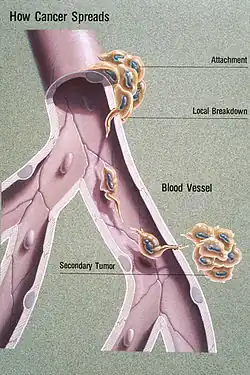

Metastasis is the spread of cancer to other locations in the body. The dispersed tumors are called metastatic tumors, while the original is called the primary tumor. Almost all cancers can metastasize.[40] Most cancer deaths are due to cancer that has metastasized.[41]

Metastasis is common in the late stages of cancer and it can occur via the blood or the lymphatic system or both. The typical steps in metastasis are:

- Local invasion

- Intravasation into the blood or lymph

- Circulation through the body.

- Extravasation into the new tissue

- Proliferation

- Angiogenesis

Different types of cancers tend to metastasize to particular organs. Overall, the most common places for metastases to occur are the lungs, liver, brain, and the bones.[40]

Metastasis

Metastasis is the spread of cancer to other locations in the body. The dispersed tumors are called metastatic tumors, while the original is called the primary tumor. Almost all cancers can metastasize.[40] Most cancer deaths are due to cancer that has metastasized.[41]

Metastasis is common in the late stages of cancer and it can occur via the blood or the lymphatic system or both. The typical steps in metastasis are local invasion, intravasation into the blood or lymph, circulation through the body, extravasation into the new tissue, proliferation and angiogenesis. Different types of cancers tend to metastasize to particular organs, but overall the most common places for metastases to occur are the lungs, liver, brain and the bones.[40]